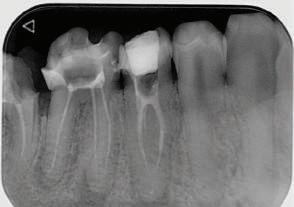

Пациентът постъпи в моята клини ка с наличие на темпоромандибуларен дисфункционален болков синдром, едно странно изместен диск с редукция в дяс ната става, клас II, подклас 2, тесни гор на и долна челюст със струпване, дъл бок овърбайт

орални снимки и снимки на позата, пал пация на мускулите, брукс-чекър, оклу зограми, кондилография, рентгеногра фии, СВСТ и ядрено-магнитен резонанс на темпоромандибуларните стави). Преди началото на ортодонтското лечение всички стари възстановява ния бяха свалени и бяха заменени с дъл госрочни временни от хибридна керами ка. На девитализираните зъби бе прове дено ендодонтско релечение. Индивиду ализиран оклузален сплинт бе направен с цел да се постигне контролирано репо зициониране на долната челюст, като носенето му продължи три месеца до възстановяване на правилната позиция на ставния диск и затихване на орофаци алната болка и дискомфорт в ставата. Брекетите в горната челюст бяха за лепени, за да започне подреждането и нивелирането на зъбите, докато паци ентът все още носеше сплинта. След края на терапията със сплинта бе на правена кондилография, за да се потвър ди триизмерната позиция на долната челюст. След залепване на брекетите в долна

тация на долната челюст. Дъга GUMMETAL с tip-back извивки бе поставена в долната челюст за ниве лиране кривата на Шпее. Случаят бе финализиран с 19x25 SS дъги в горната и долната зъбна дъга за координиране. Преди да се изготви финалният восъ чен моделаж, естетичните и лицеви те характеристики бяха анализирани с помощта на дигитален дизайн на ус мивката, за да се създаде мок-ъп, чии то форма и размери да бъдат одобрени от пациента. Бе оценена фонетиката и бяха заснети лицеви снимки и видеа. Зъ бите бяха изпилени, като препарация та бе изцяло водена от функционалния восъчен моделаж, прехвърлен в устата на пациента. След препарацията восъч ният моделаж бе напаснат и насложен върху препарационния модел и бе фрезо ван от e-max multi bl 1. Циментирането на финалните конструкции бе направе но при изолация с кофердам, следвайки адхезивния протокол. След циментирането бе направено проследяване на оклузията чрез снема не на отпечатъци, монтиране на моде лите в артикулатор в окончателната интеркуспидация и внимателно прове ряване за наличие на блокажи при воде ни движения.

В конкретния случай комбинирах златния стандарт при статична по зиция с динамична оценка на функци ята на темпоромандибуларната ста ва, за да диагностицирам и лекувам ней ната дисфункция.